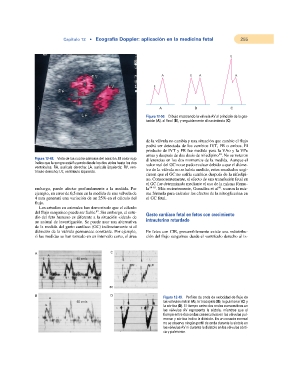

Figura 12-50. Dibujo mostrando la válvula AV al principio de la ges-

tación (A), al final (B), y seguidamente al nacimiento (C).

B 80 Figura 12-49. Perfiles de onda de velocidad de flujo de

A D las válvulas mitral (A), la tricúspide (B), la pulmonar (C) y

la aórtica (D). El tiempo entre dos ondas consecutivas en

E 50 cm/s las válvulas AV representa la sístole, mientras que el

tiempo entre dos ondas consecutivas en las válvulas pul-

monar y aórtica indica la diástole. En un corazón normal

no se observa ningún perfil de onda durante la sístole en

las válvulas AV ni durante la diástole en las válvulas aórti-

ca y pulmonar.